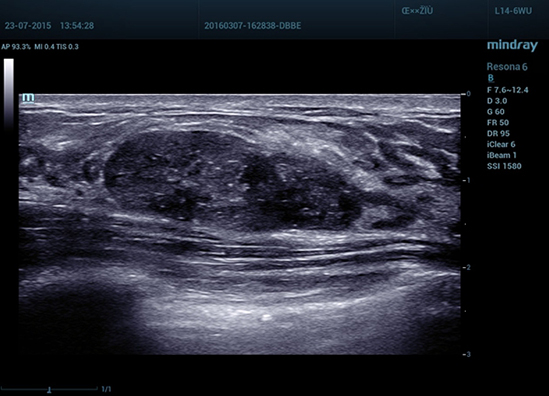

Метод эластографии Natural Touch

Natural Touch обеспечить непревзойденную чувствительность и отличную воспроизводимость результатов вне зависимости от навыков оператора, повышает клиническую значимость метода и расширяет возможности его применения. Уникальный анализ зоны ободка — исключительно полезный инструмент для оценки доброкачественных и злокачественных образований— предоставляет данные о коэффициенте деформации между окружающей тканью и пораженным участком, что позволяет оценить степень инфильтрации раковых клеток в окружающие опухоль ткани.

1-R6-img7

• 03 Fibroadenoma of Breast

Фиброаденома молочной железы